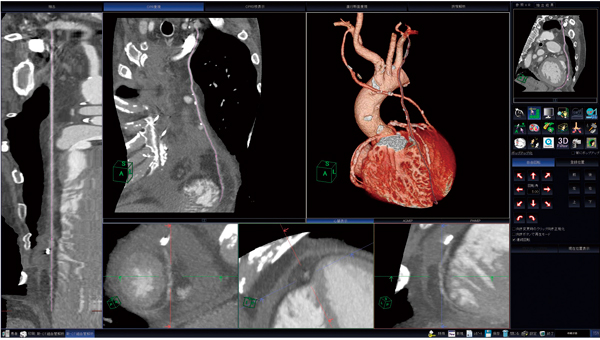

また,冠動脈解析技術は,その高進に伴い,PCIや冠動脈バイパス術の術前・術後の冠動脈ならびにバイパスグラフトの評価に応用されている。冠動脈CTの適応患者は,急速に増加している。本稿では,冠動脈バイパス術術後評価において,最適な吻合部解析を可能にする冠動脈バイパスグラフト解析ソフトウェアを紹介する(図1)。

図1 CT細血管解析ソフトウェアによる冠動脈バイパスグラフト解析